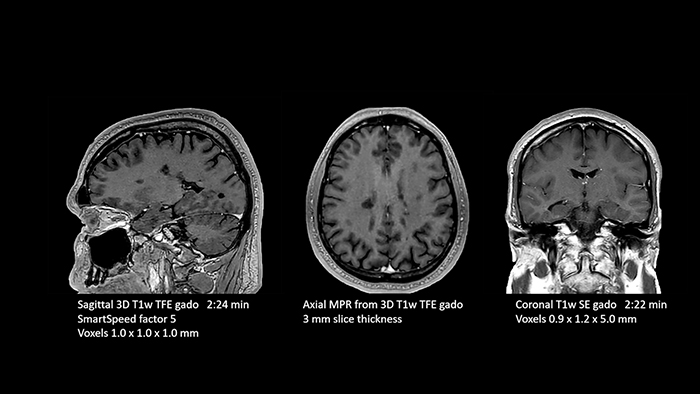

In this examination SmartSpeed is used to reduce scan times. All three FLAIR orientations were obtained with only one 3D sequence using SmartSpeed. Performed with 1.5T Ambition X, dS Head coil.